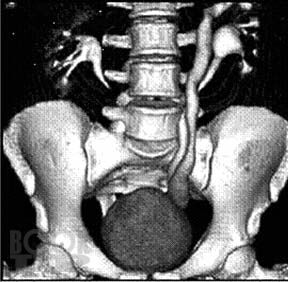

Аномалии развития почек: диагностика и лечение

Изложены вопросы этиологии, патогенеза, классификации, диагностики и лечения аномалий развития почки. Отдельным разделом представлены сведения о кистозных образованиях почки, как наиболее частых заболеваниях почечной структуры, имеющих тенденцию к злокачественному перерождению и требующих дифференциальной диагностики с онкологическими процессами в почке. Детально освещены диагностика и современные малоинвазивные методы лечения простых кист.